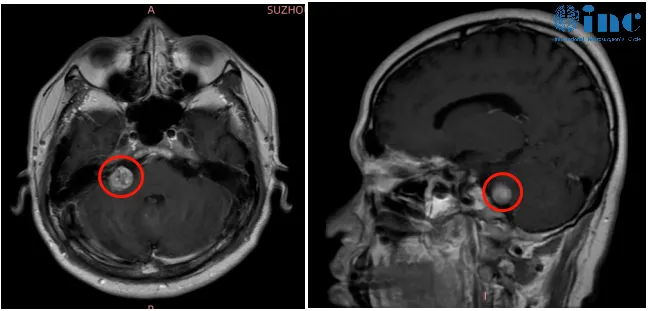

进一步的检查给出了明确答案——右侧桥小脑角区发现结节,考虑为听神经瘤。那一刻,高教授意识到:突发性耳聋并非病因,而是肿瘤发出的“预警信号”。

听神经瘤是桥小脑角区最为常见的良性肿瘤。尽管性质为良性,但其生长位置极为特殊,紧邻面神经、听神经及重要血管。随着肿瘤体积增大,将持续压迫神经,不仅导致听力出现不可逆下降,还会引发耳鸣、眩晕、行走不稳等一系列症状。

听神经瘤手术发展至今已逾百年历史。伴随神经外科技术的飞速进步,当前手术核心目标已从“保全生命”升级为“保全功能、完全切除肿瘤、防止复发”。然而,内听道型听神经瘤的手术难度依然极高:肿瘤深藏于内听道内部,需要磨除周围骨质方能充分暴露。面神经直径仅1-2毫米,薄如蝶翼,极易受损。想要同步实现“肿瘤全切、保留面神经功能、保留听力”,对主刀医生的技术水准与临床经验提出了近乎苛刻的要求。

高老师的肿瘤生长于内听道深处,位置刁钻。接诊医生坦言:若想实现肿瘤全切且不复发,手术过程中需磨除骨质,极易损伤面神经与听神经。

仅仅四个月后,至2022年初,其右耳听力再次出现“中断”。更糟糕的是,他开始感到行走不稳,并出现轻微眩晕症状。此时,手术治疗从“可选项”转变为“必选项”。但一个核心问题横亘于前:如何在彻底切除这个位置刁钻的肿瘤的同时,保全他作为教师职业所需的“面部容貌与功能”?